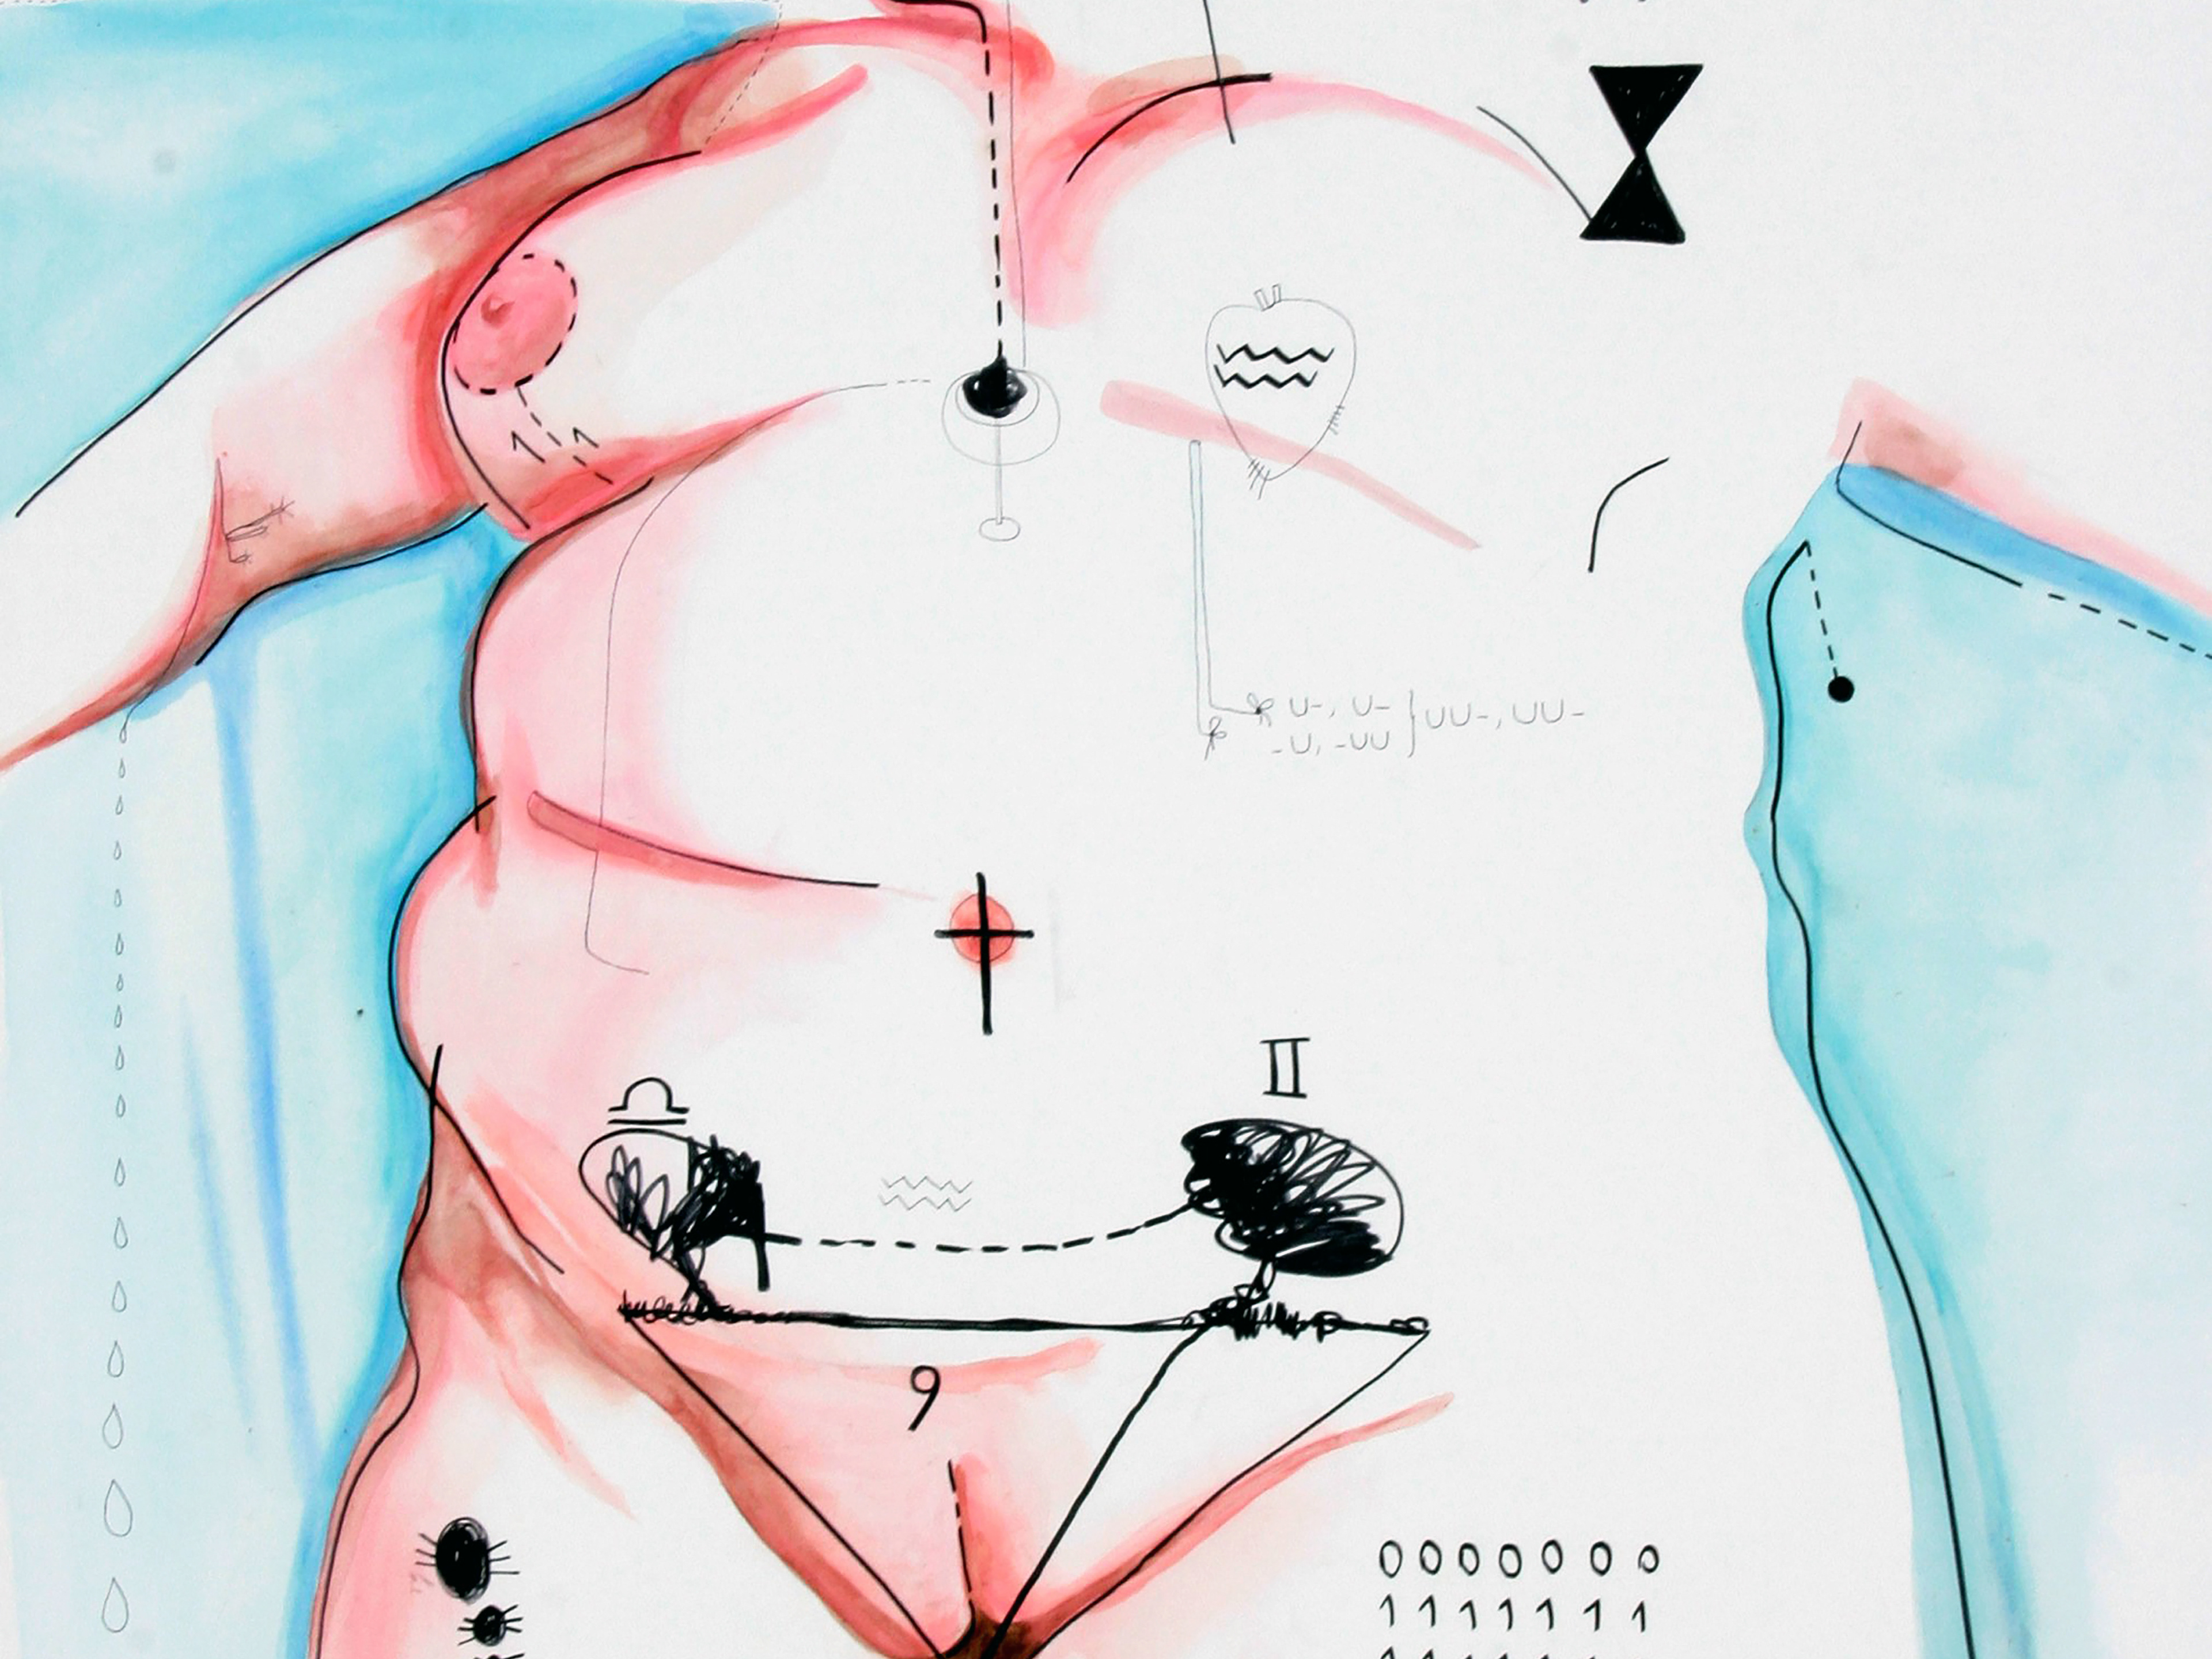

Traccia siderale di un corpo in attesa

“Inner Constellation” nasce da una sospensione, da uno strappo.

Nel 2013, una trombosi venosa profonda al braccio destro interrompe brutalmente il mio lavoro. Perdo l’uso dell’arto con cui disegnavo, e con esso, una parte di me.

In quel vuoto, restano i frammenti: ultimi disegni automatici, venuti alla luce poco prima dell’evento. Li raccolgo, li conservo, li affido al silenzio.

Sette anni dopo, nel 2019, torno a loro. Li riassemblo, li affido a cornici nere come orbite, e compongo una costellazione interiore: ogni frammento è una stella della mia mappa invisibile, un punto luminoso che testimonia il percorso tra la perdita e il ritrovamento, tra corpo ferito e corpo riattivato.

Un referto medico, reale ma trasfigurato, completa l’opera: da documento clinico diventa oggetto simbolico, materia mutata.

Questa costellazione non cerca risposte. È un enigma che pulsa, che resta.

È il disegno della mia sopravvivenza.

A sidereal trace of a body in suspension

“Inner Constellation” was born from a rupture, a suspension.

In 2013, a deep vein thrombosis in my right arm abruptly halted my work. I lost the use of the arm I used to draw — and with it, a part of myself.

What remained were fragments: the last automatic drawings, created just before the event. I kept them, entrusted them to silence.

Seven years later, in 2019, I returned to them. I reassembled them, framed them in black as if in orbits, and composed an inner constellation: each fragment a star in my invisible map, a glowing point charting a journey through loss and re-embodiment.

A real medical report, radically transformed, completes the piece. No longer a clinical object, it becomes symbolic material — transfigured matter.

This constellation seeks no answers. It is an enigma that pulses, that remains.

It is the drawing of my survival.